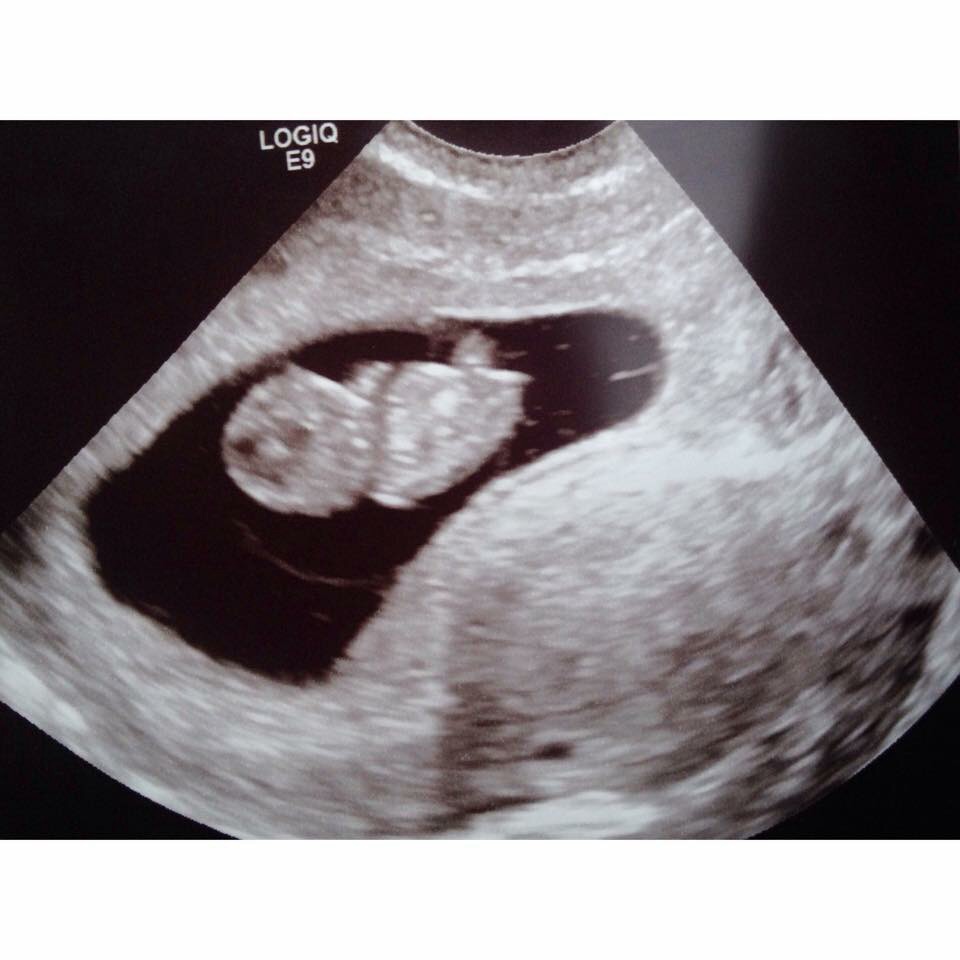

We had our first ultrasound. We had vaginal and abdominal sonograms. Bug is measuring at 9 weeks give or take a few days. So right now they moved it two July 12th but might change again. He or she had an awesome heart beat 160! He or she is super healthy the tech said from looks of it all. One ovary is in larger from hormones she said looked like. If it hasn't gone down by next ultrasound they may take more time look at it. All is well with us! How was everyone else first ultrasound?